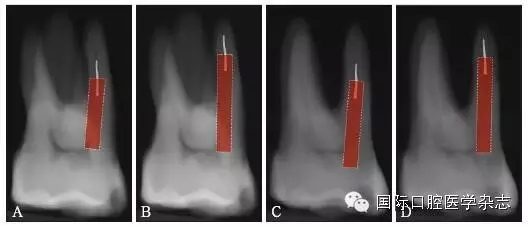

3.2.5 取出難度評(píng)估 多數(shù)情況下,如果分離器械上1/3能夠暴露,通常能夠取出。位于直根管、近根管口的分離器械較位于彎曲根管的器械容易取出。位于根管通暢部分的分離器械通??梢匀〕?。如果分離器械位于根管彎曲附近,并且牙本質(zhì)厚度容許建立從根管口到器械冠方的通道以接近其冠部末端,而不至于產(chǎn)生穿孔等并發(fā)癥,則仍有可能將其取出。在這些病例中,都必須建立到達(dá)分離器械上部的直線通路。如果器械分離于彎曲根管的根尖部,則很難建立安全的通道,且分離器械移動(dòng)可能造成器械超出根尖孔,風(fēng)險(xiǎn)較大,通常不太可能將其去除(圖8)。

A:分離器械位于較直的根管中上部分,較容易取出;B~D:分離器械位于根管彎曲之下或彎曲根管近根尖部,無法取出。

圖 8 取出難度的評(píng)估